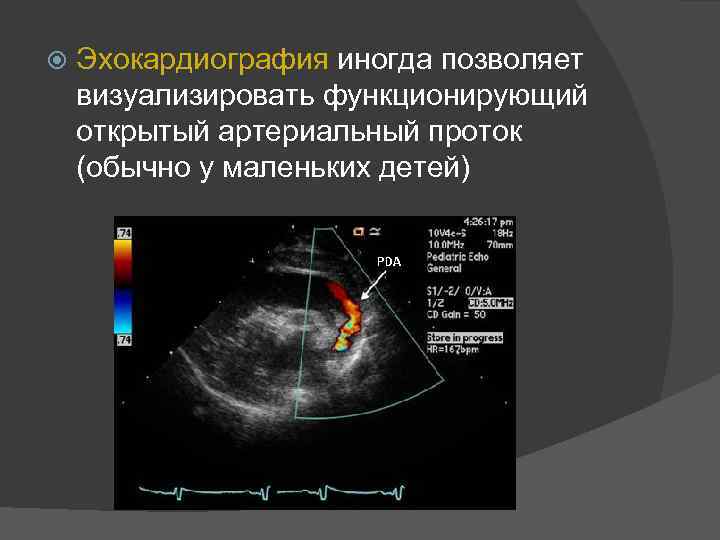

Эхокардиография иногда позволяет визуализировать функционирующий открытый артериальный проток (обычно у маленьких детей)